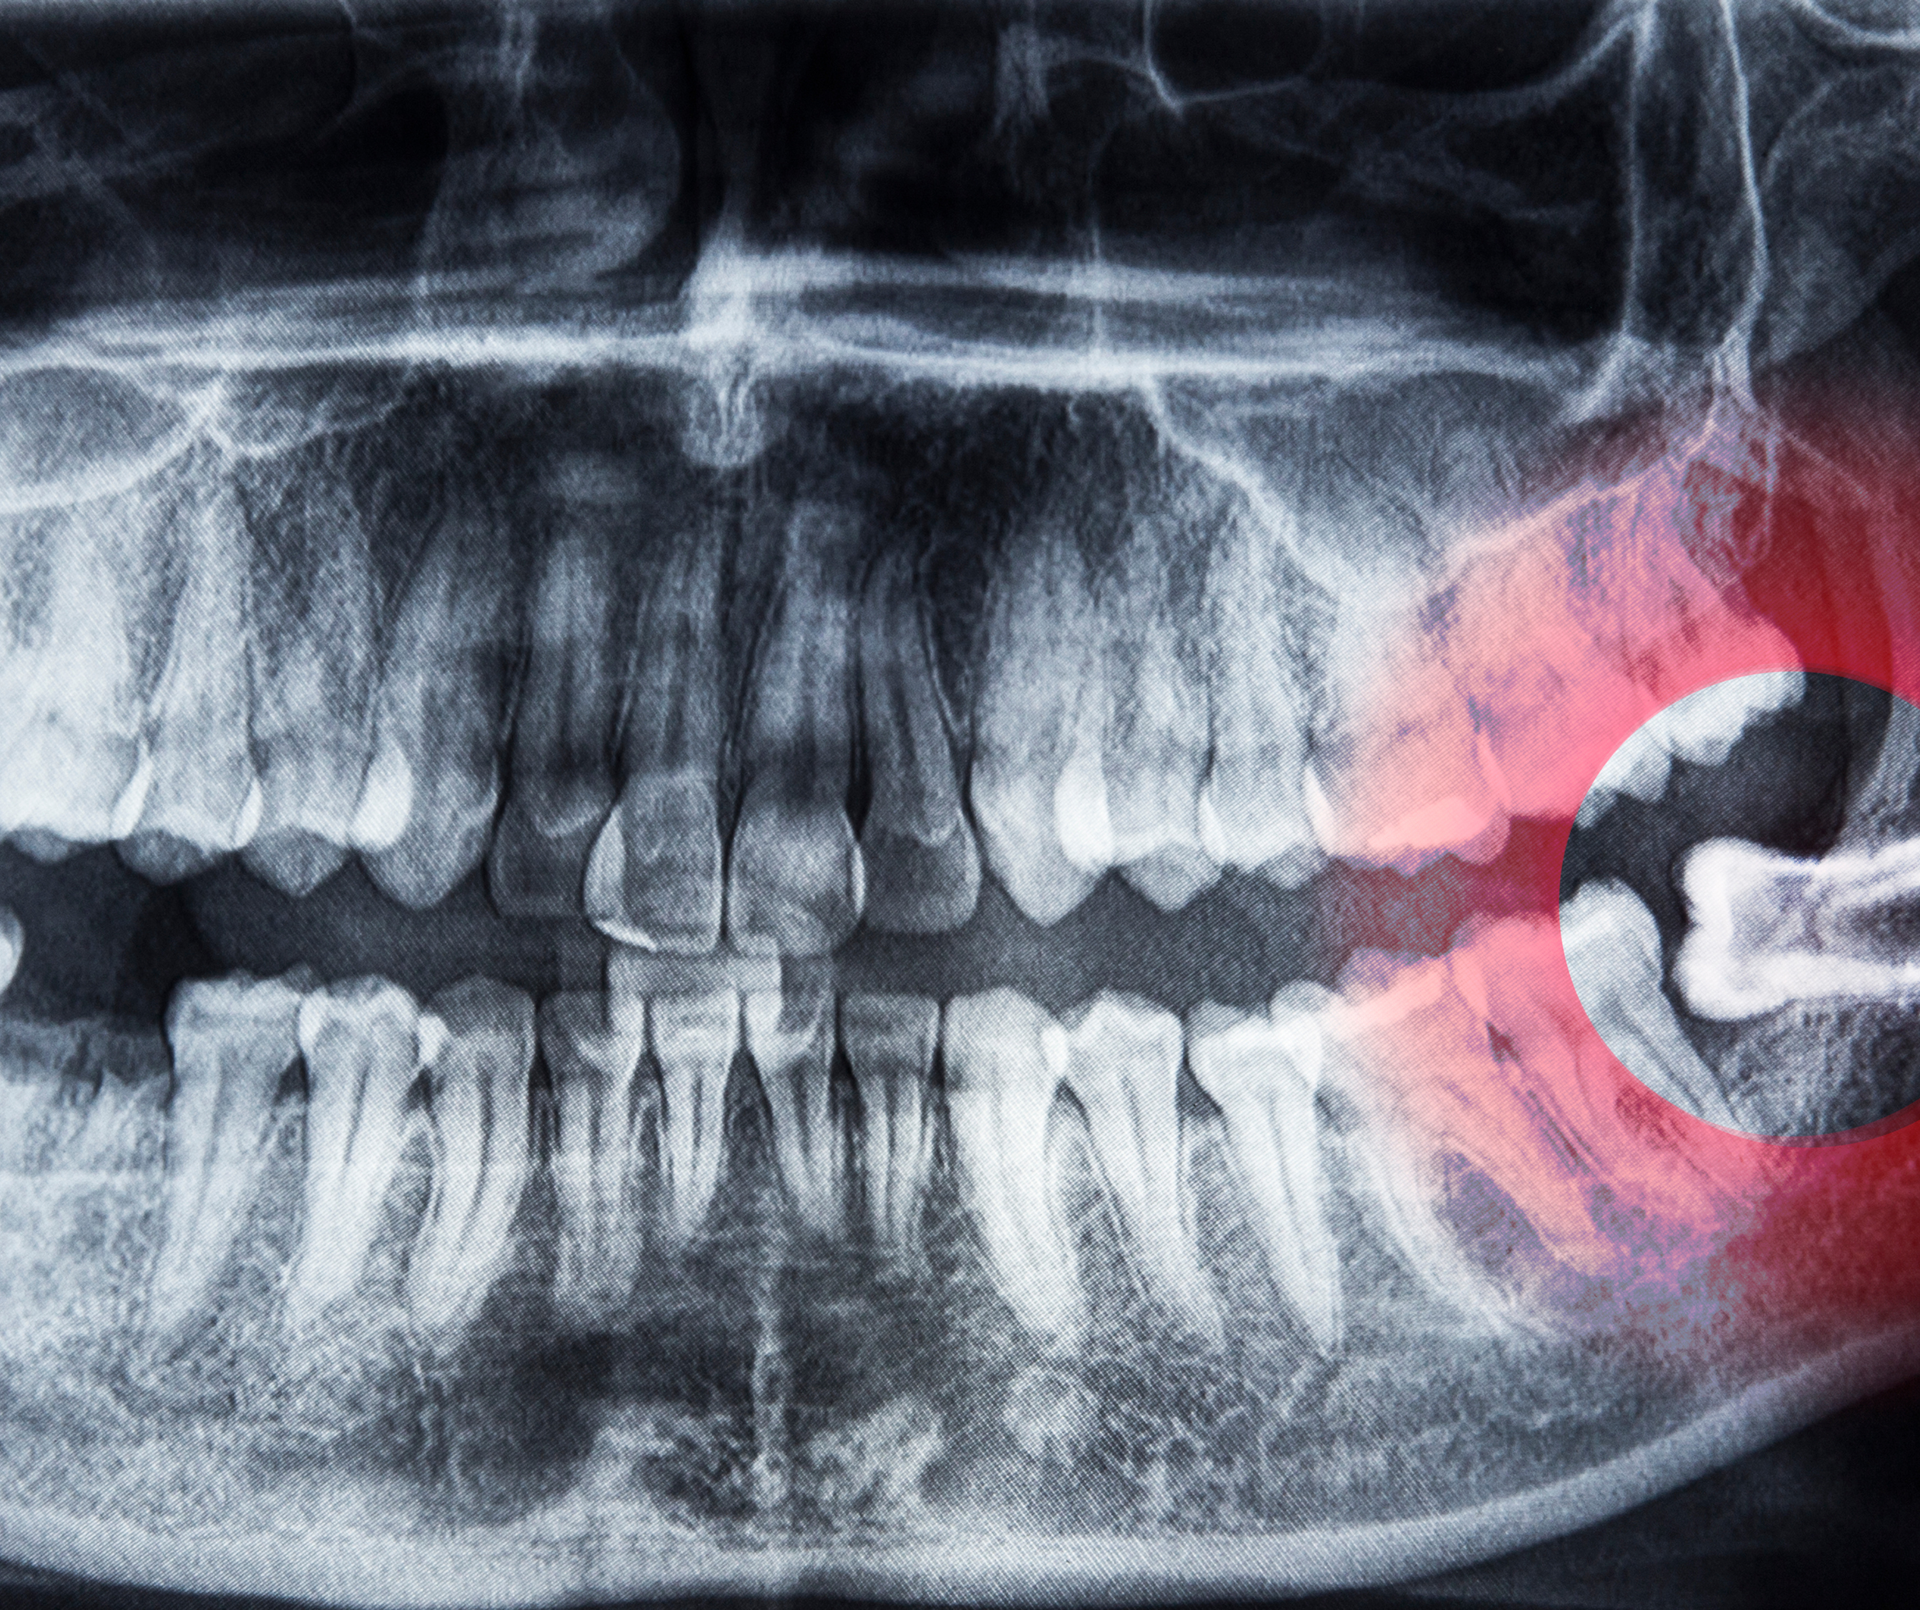

- Narrow jaw development or misalignment

For instance, a child who habitually breathes through their mouth may not only struggle with dry mouth or poor sleep, but also develop a narrow jaw and crowded teeth over time. Addressing muscle function in these cases can support more stable orthodontic outcomes and reduce the risk of relapse after braces.